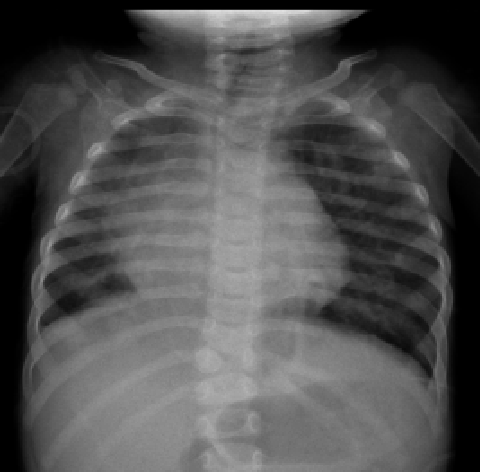

Radiografía de Tórax en Pediatría

La radiografía de tórax constituye la modalidad de imagen más empleada en la evaluación del tórax de pacientes pediátricos, desde recién nacidos hasta adolescentes. Esta prevalencia se explica por su…